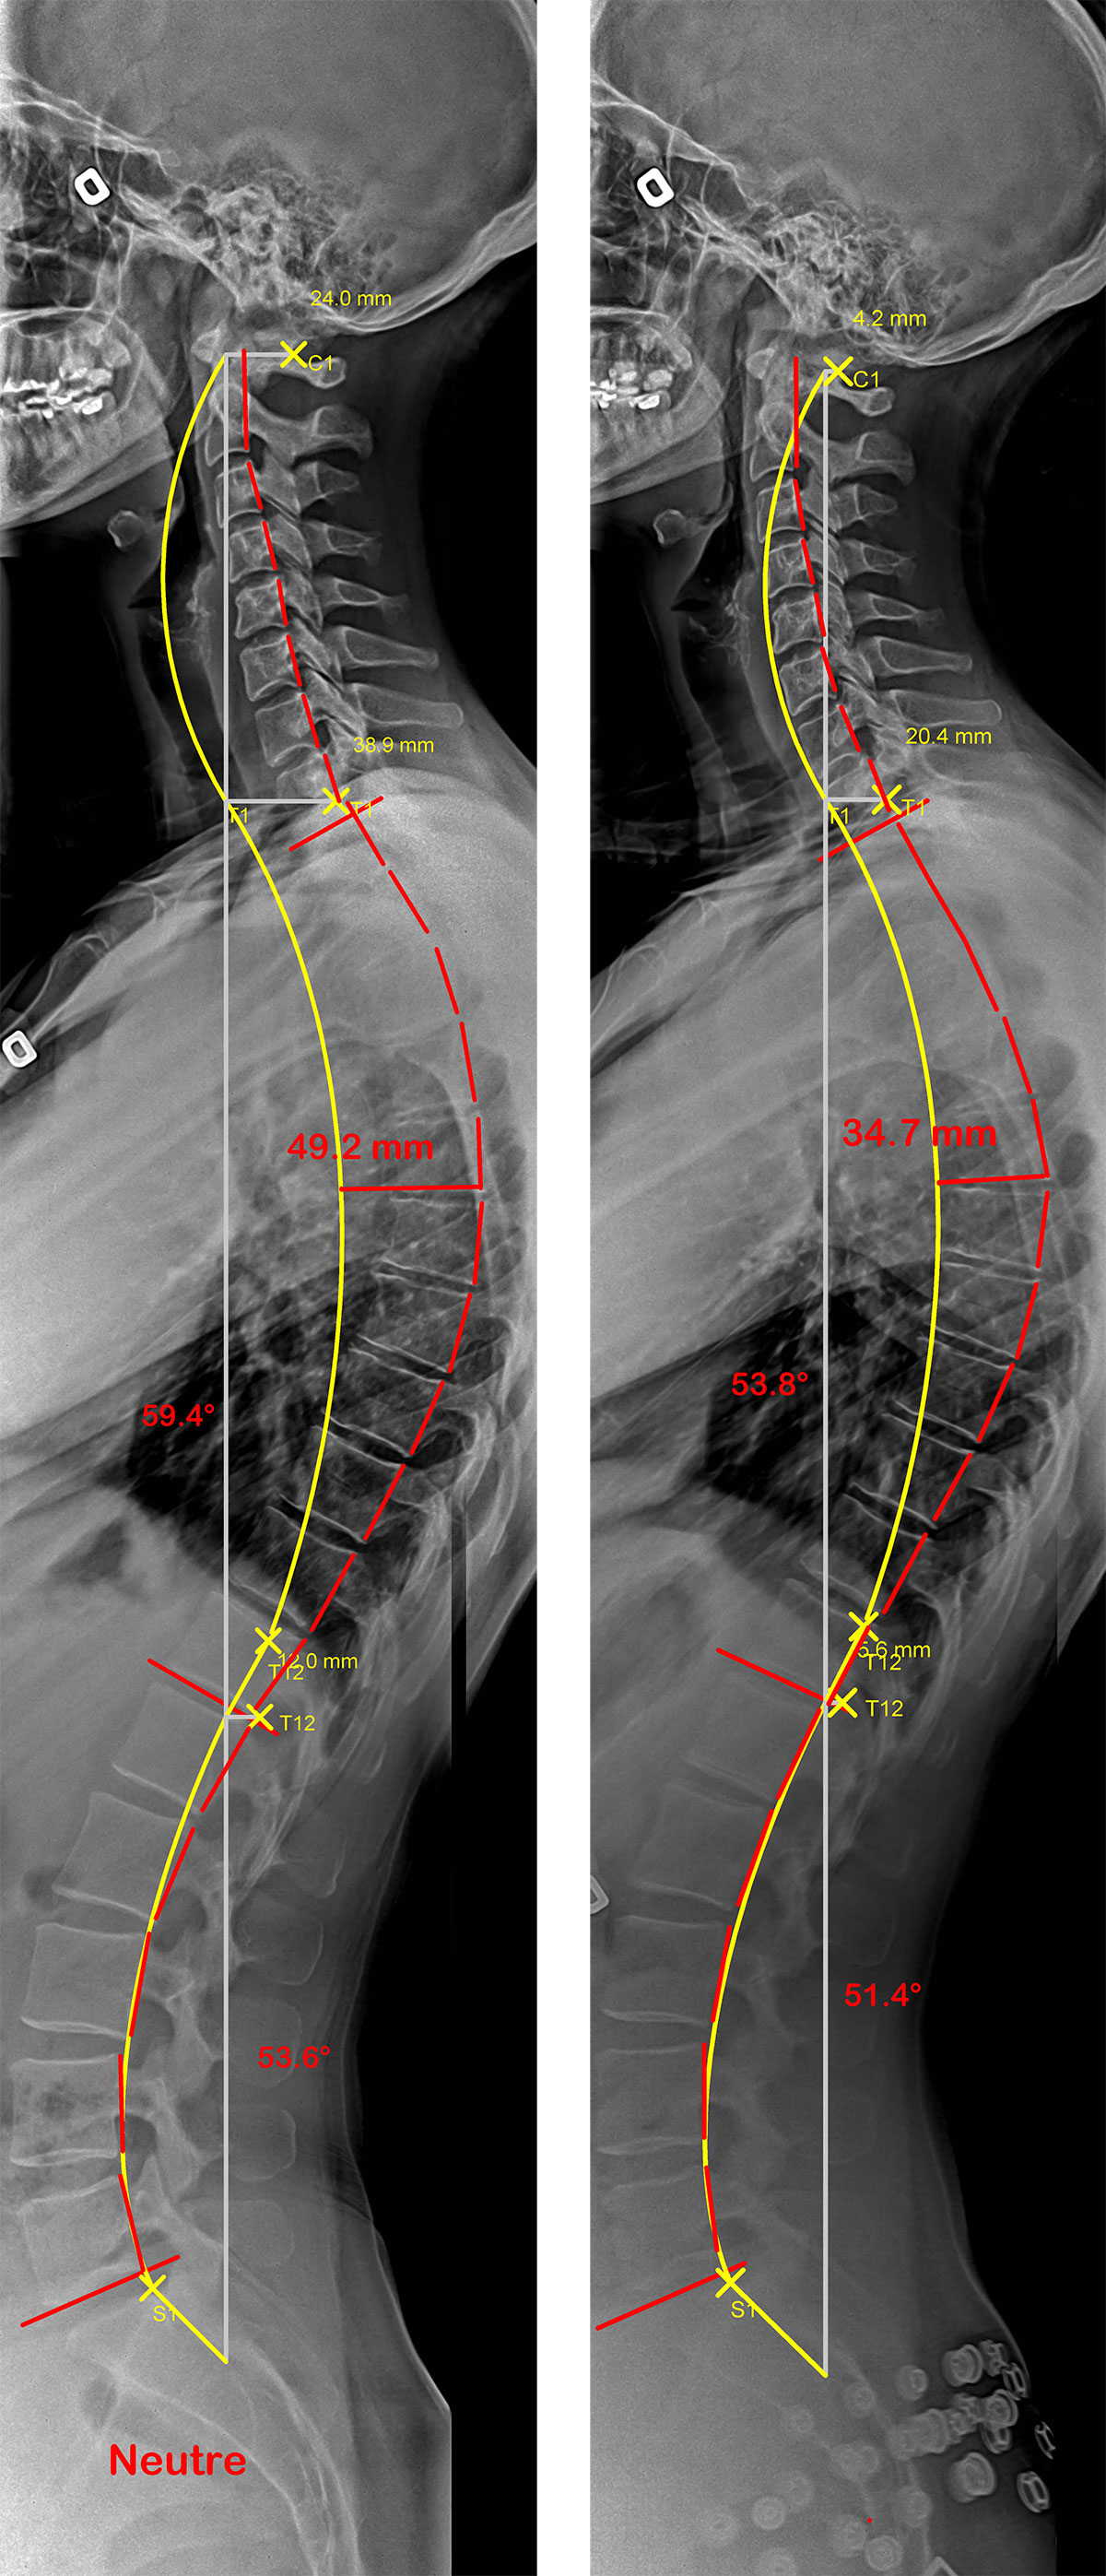

Colonne vertébrale d’un adulte souffrant d’hypercyphose, sans et avec SpineCor®

Radiographies de profil d’un patient présentant une hypercyphose. La ligne jaune représente la courbure idéale et la rouge, celle formée par la colonne vertébrale du patient. Dans la seconde radiographie où le patient porte son SpineCor®, on remarque une amélioration significative de la courbe anormale.